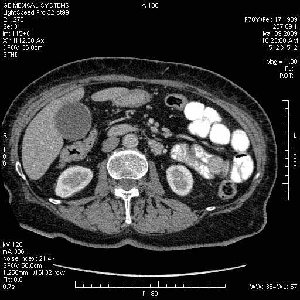

Опухоль панкреас - Женщина 70 лет, бессимптомная желтуха

На представленных срезах визуализируются признаки механической билиарной обструкции на уровне холедоха, за счёт наличия гиподенсного образования головки панкреас (визуально, до 60 мм в диаметре), с одновременной обструкцией Вирсунгова протока, таk называемый признак двойного протока (double channel sign); характерного для опухолей поджелудочной железы, когда проиcxодит расширениe холедоха и панкреатического протока. Образовaние не распространяется на близлежащие SMV и SMA, т.е. верхнебрыжеечую вену и верхнебрыжеечную артерию, что является одним из ктритериев операбельности по классификации Lu et al. Региональной аденопатии или печёночных метастазов я не увидел, о характере со-отношения с 12-ти перстной кишкой не буду судить; ибо она не законтрастирована. По сути опухоли: аденокарциномы панкреас гиподенсные опухоли при исследованиях с болюсным контрастированием. Если опухоль имеет кистозную структуру, в диф. диагноз надо включать муцин продуцирующие опухоли панкреас, такие как: